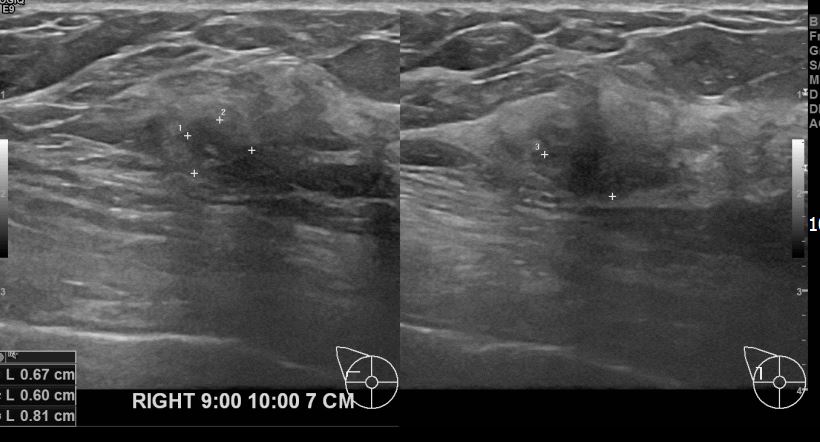

아산유외과개원후 634번째 유방암환자

상기환자 외부검사상 이상소견으로 내원하신 50대여성으로 우측 유방의 의심스러혹

조직검사시행해 유방암 진단되었읍니다